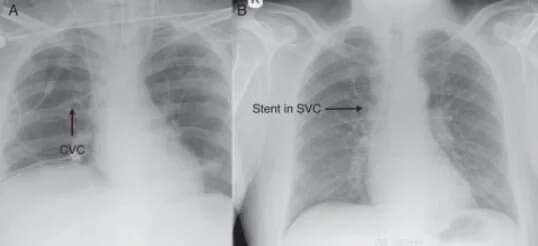

Malpositioned central venous catheter: Step wise approach to avoid ...

Lines and Tubes What are the common lines